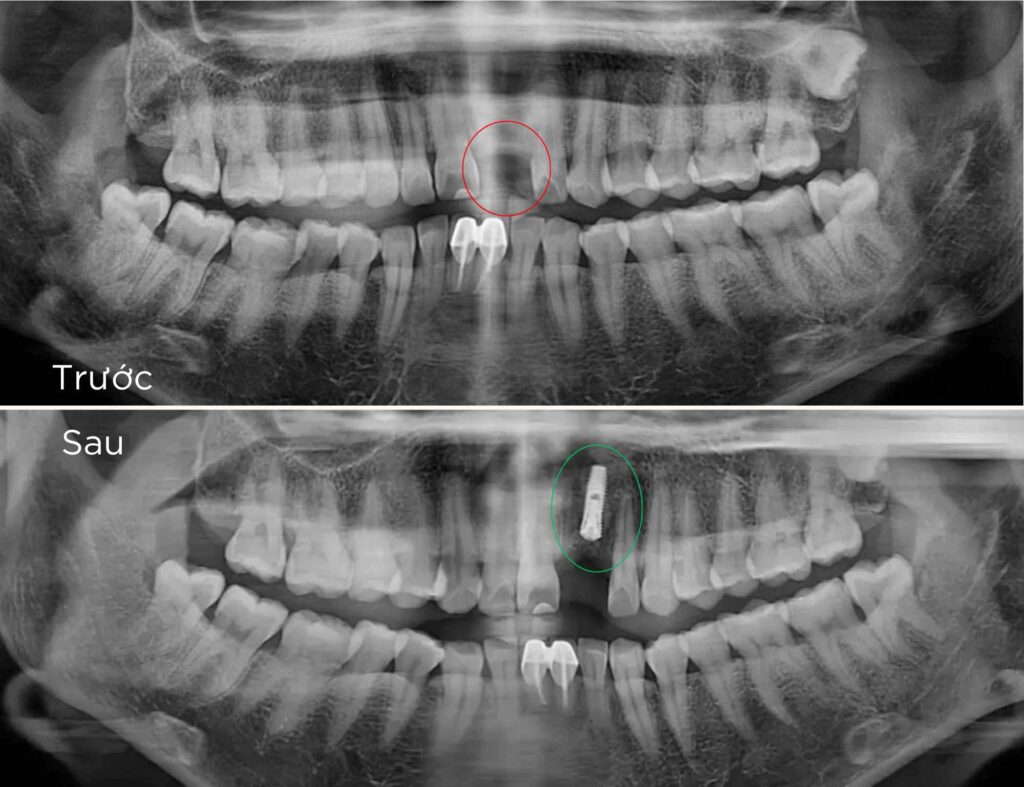

là phương pháp phục hồi răng mất tiên tiến, sử dụng trụ chụ chân răng nhân tạo – Implant từ titanium cấy vào xương hàm để thay thế chân răng đã mất. Sau đó, một mão răng sứ được gắn lên trụ, tạo ra chiếc răng mới với hình dáng và chức năng giống như răng thật.